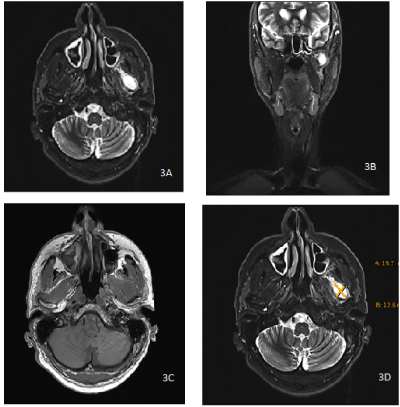

Panoramic X-ray was rendered by the dentist and showed no destruction of the TMJ region (Figure 1 and 2). CT and MR scans sent by the referring ENT showed a mass of 20 x15 x12 mm size.

In detail, CT showed a partially eroded mandibular condyle with an adjunct lesion with borderline contrast agent uptake and a central hypodense region with a size of about 2.1 x 1.9 cm. MR showed a partially cystic lesion within the pterygoidal muscles anterior to the left mandible condyle (Figure 3 a-d).

Figure 3. Preoperative magnet resonance tomography with hyperintense lesion anterior to the temporomandibular joint left